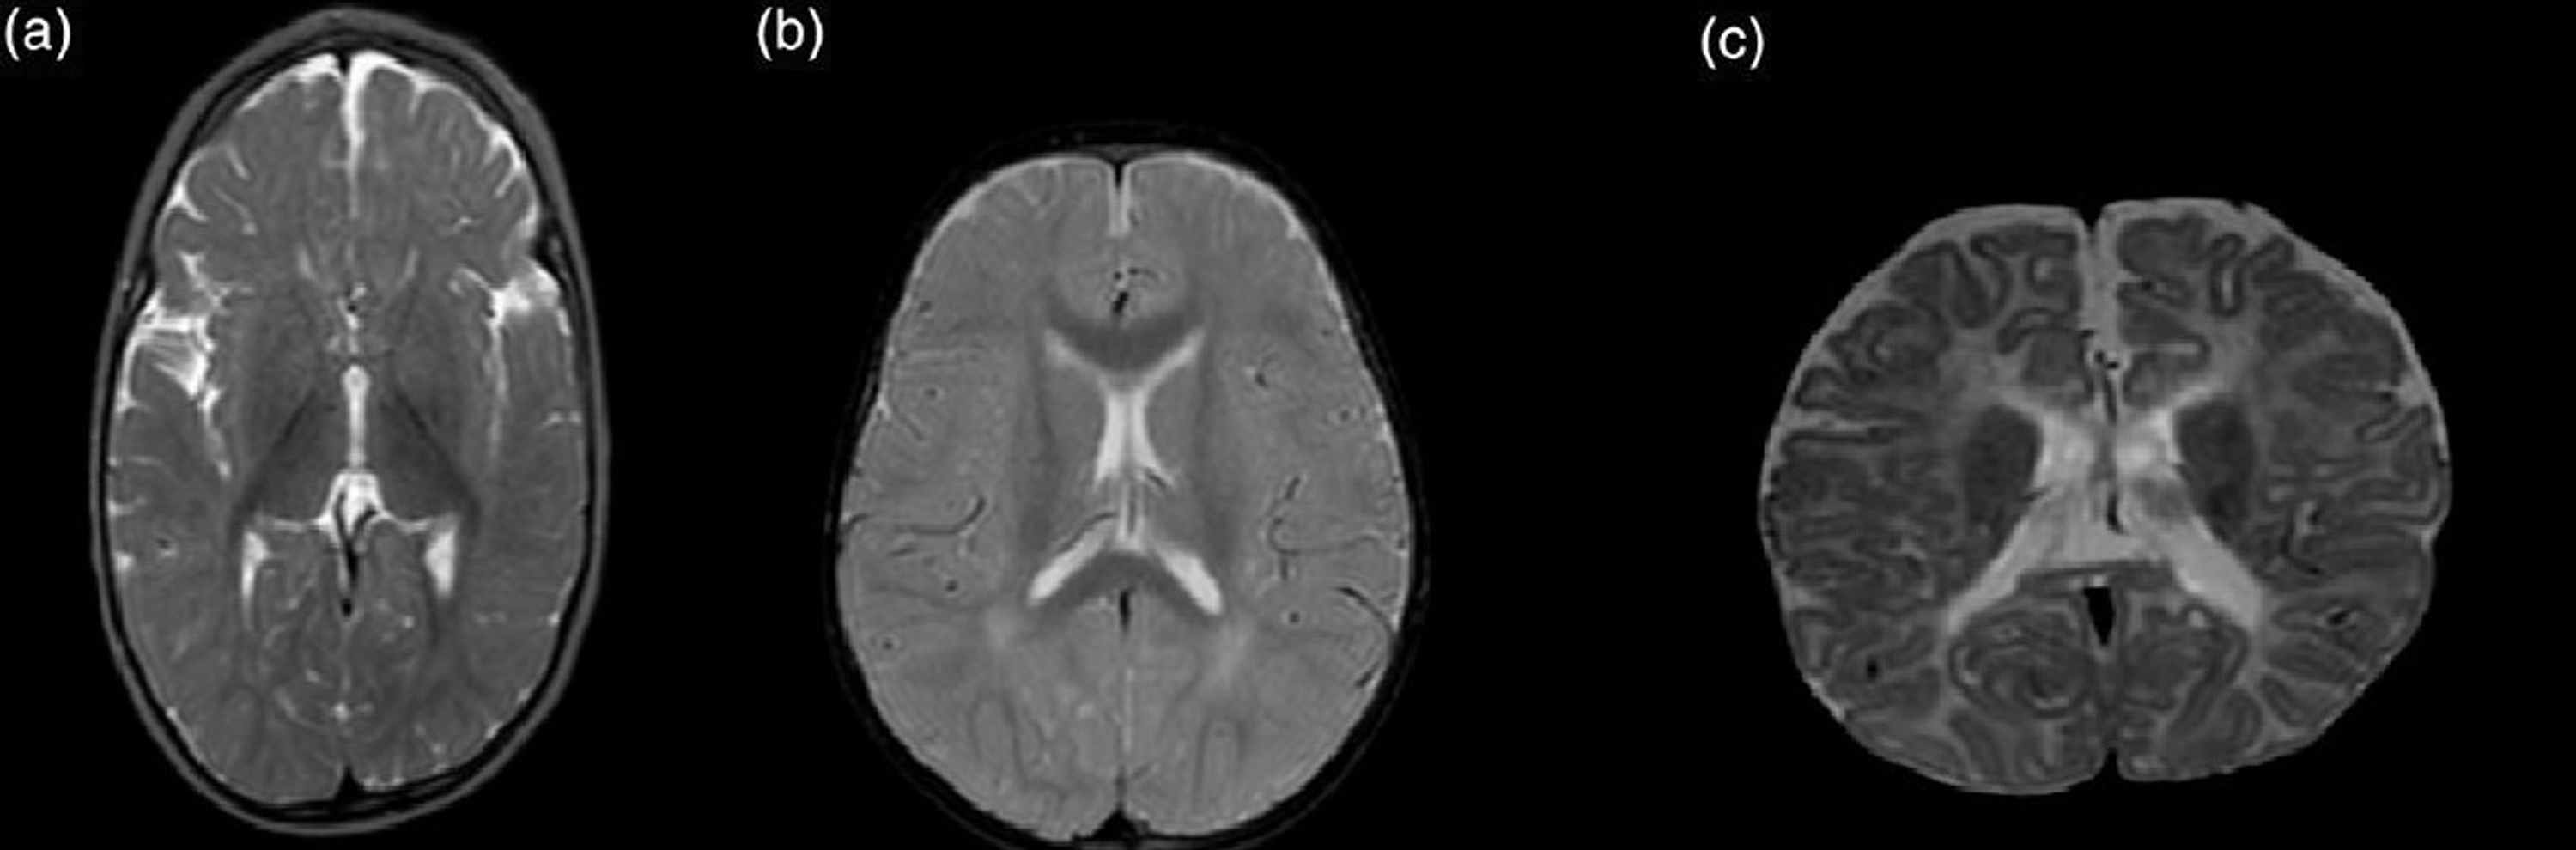

Figure 1 from Seizures during treatment of Vitamin B12 deficiency Can Vitamin B12 Cause Seizures in infants, vb12 deficiency may be characterized by signs of developmental delay, such as irritability, apathy, ataxia,. the aim of the present study was to investigate the effect of levetiracetam on plasma homocysteine,. The only vitamin deficiency known to cause or worsen seizures is a. do vitamin deficiencies cause or worsen seizures? In the article, natural approaches. Can Vitamin B12 Cause Seizures.